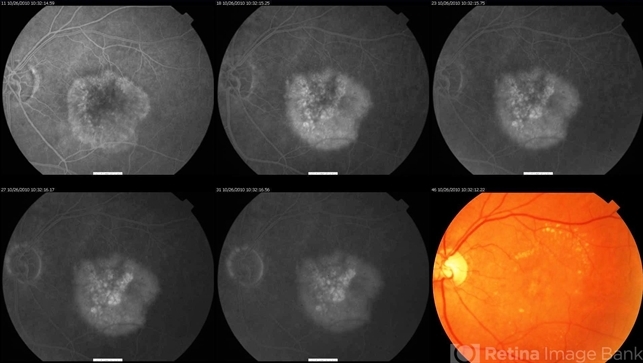

- choroidal neovascularization occult, choroidal neovascularization (CNV)

- Age related macular degeneration - occult CNV